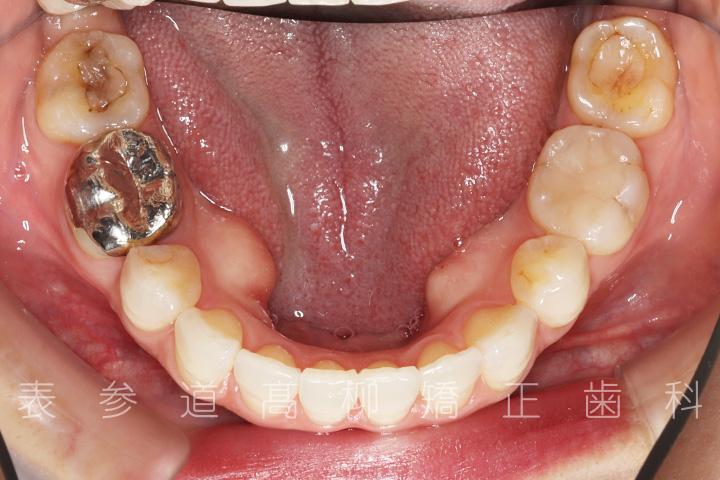

口呼吸と舌癖で前歯が咬み合わない患者様の症例をご紹介いたします。

・前歯部開咬

・上顎前突(前歯の前方傾斜)

・上下前歯部叢生(凸凹歯並び)

・口呼吸、舌癖

・上下両側第二小臼歯を抜歯